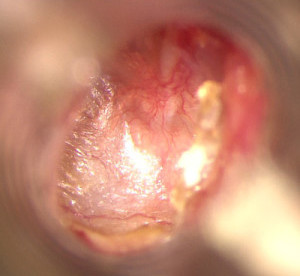

• Отоскопия. В ходе такого исследования специальными инструментами обследуется наружный слуховой проход. С его помощью можно выявить наличие вредных элементов в области барабанной перепонки, а также определить, насколько сузился костный отдел слухового прохода.